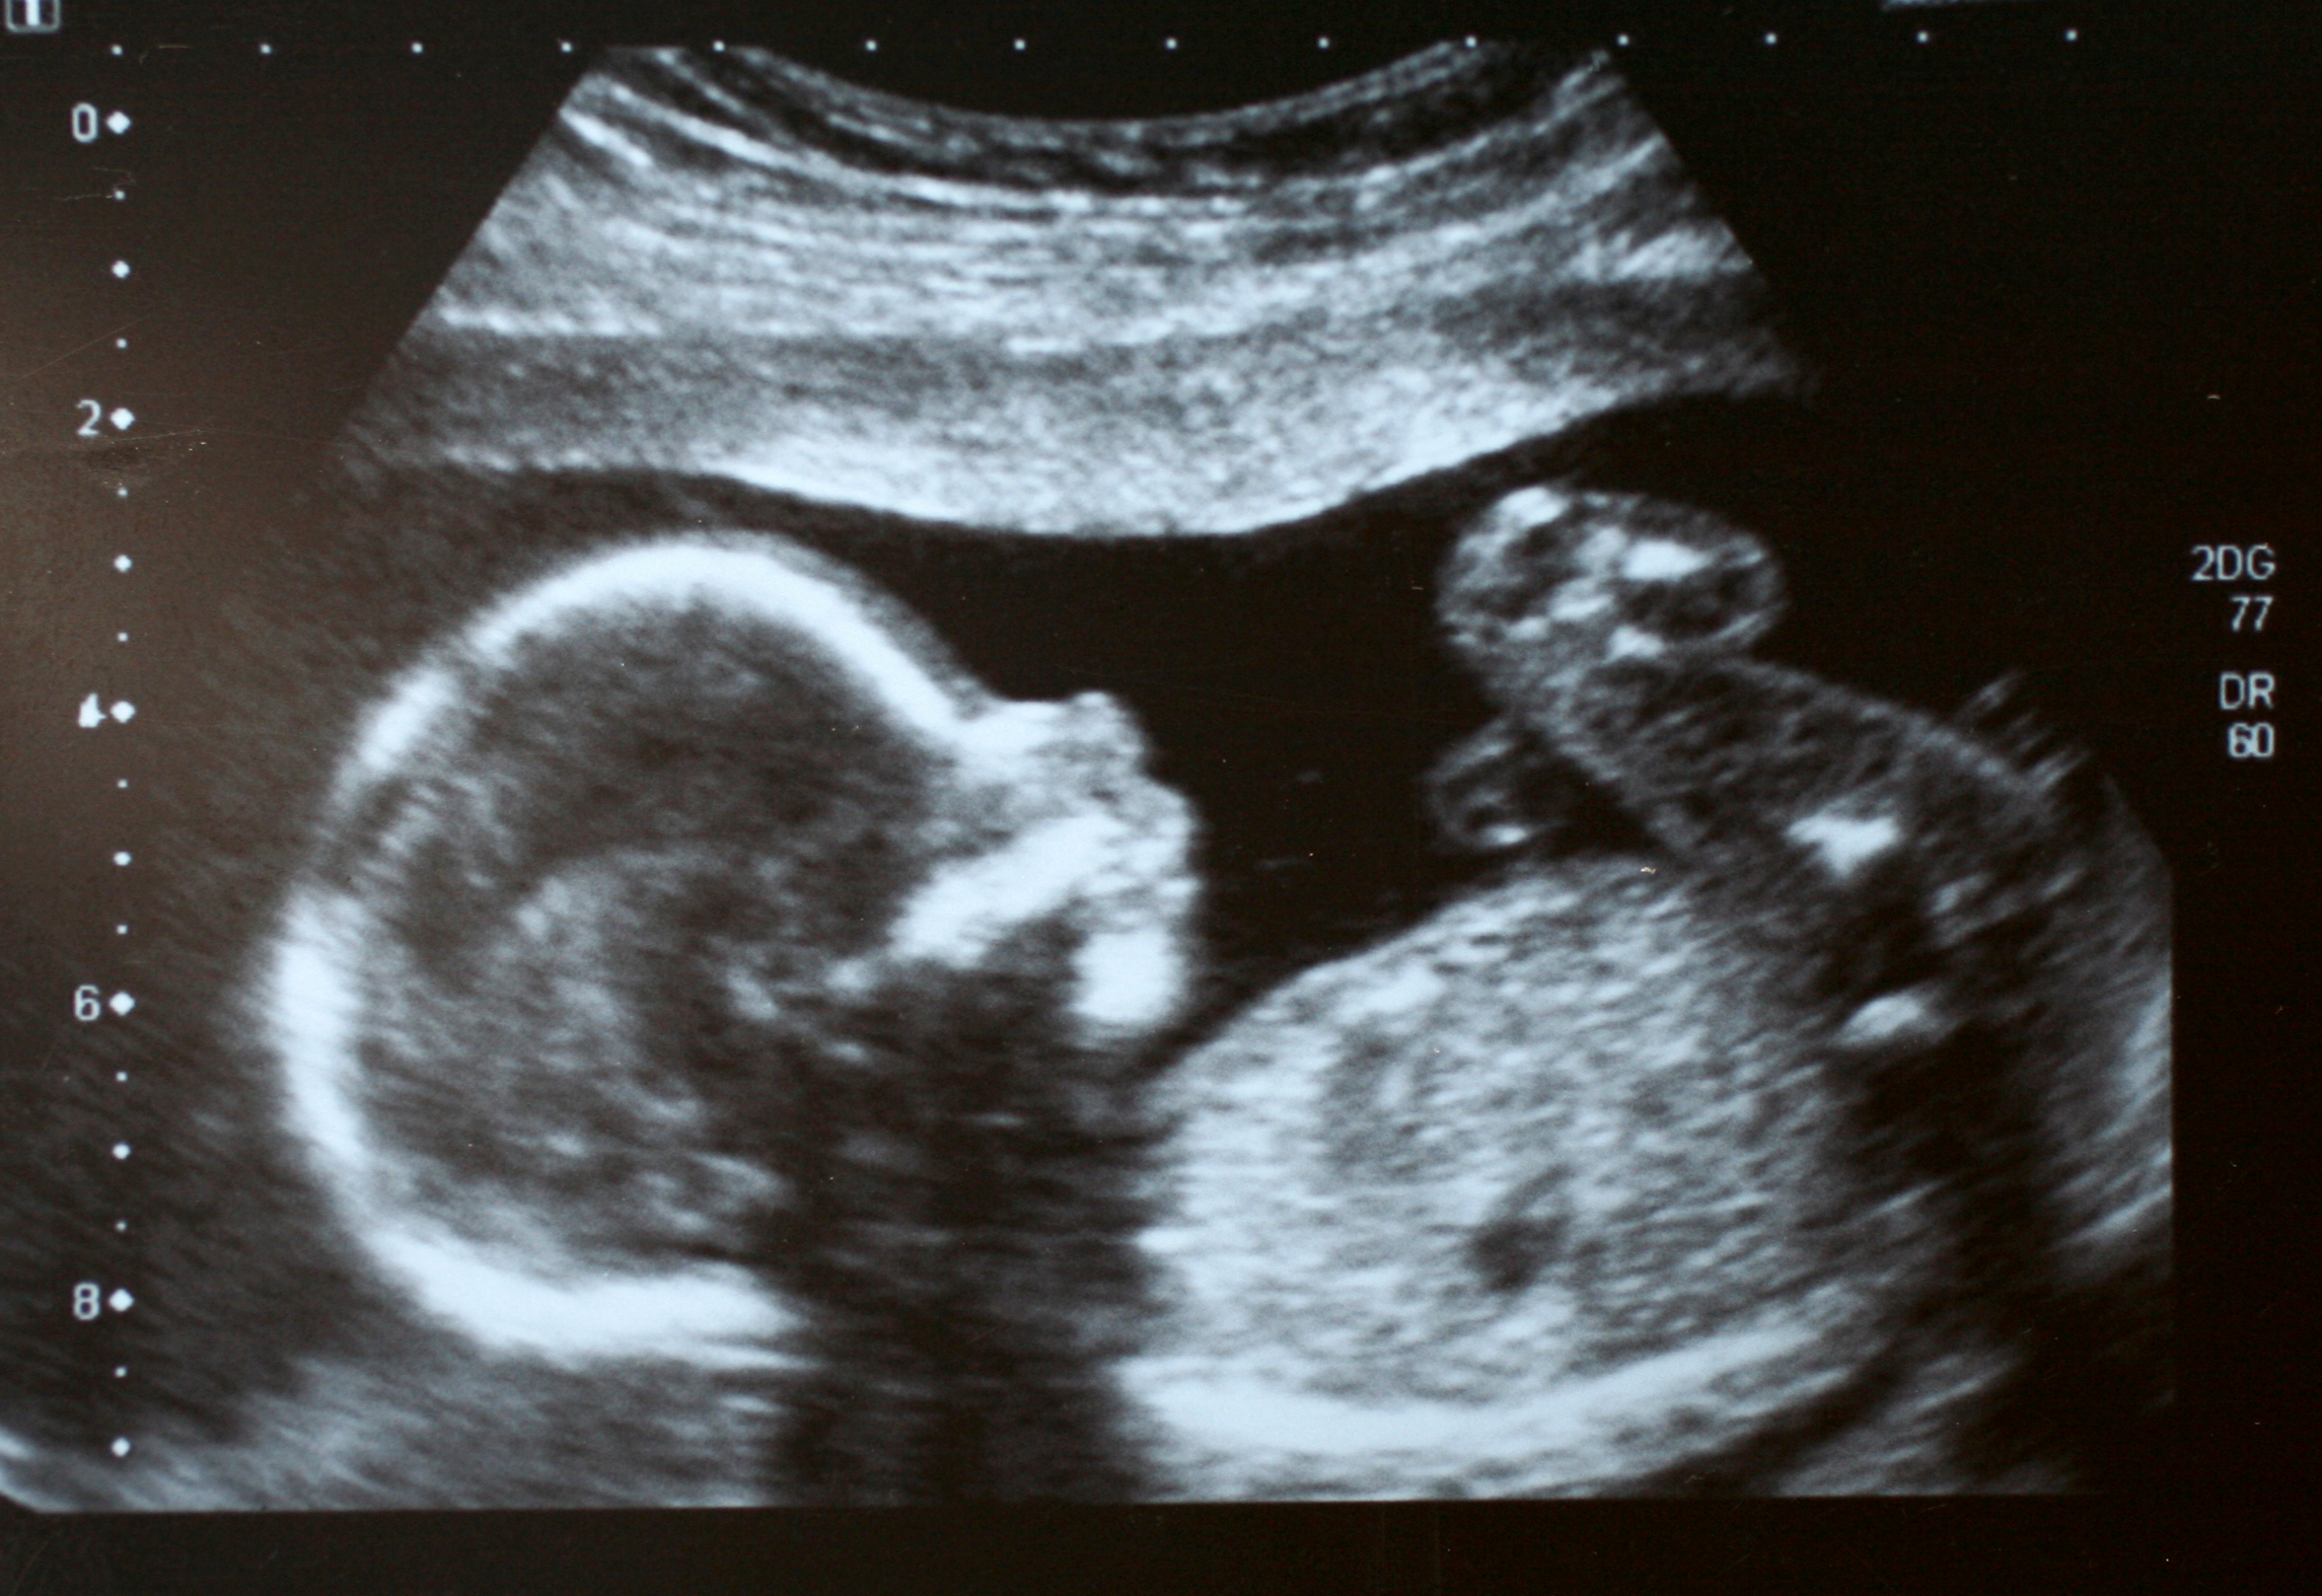

Son muchos los problemas inesperados que pueden aparecer durante el trabajo de parto y que pueden poner en jaque la salud de la madre y/o del bebé. De hecho, estos problemas son, de acuerdo a la OMS, la principal causa de muerte perinatal en países en vías de desarrollo.

Una de las razones principales de complicaciones en el momento de dar a luz es el conocido como parto obstruido, definido por la Organización de la Salud como “trabajo de parto en que la parte de presentación del feto no puede progresar en el canal del parto, a pesar de las contracciones uterinas adecuadas”. Es, de hecho, la principal causa de cesárea no programada.